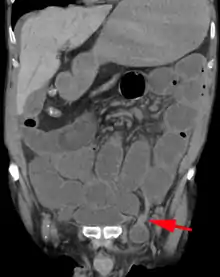

An incarcerated inguinal hernia as seen on cross sectional CT scan

A frontal view of an incarcerated inguinal hernia (on the patient's left side) with dilated loops of bowel above.

There are two types of inguinal hernia, direct and indirect, which are defined by their relationship to the inferior epigastric vessels. Direct inguinal hernias occur medial to the inferior epigastric vessels when abdominal contents herniate through a weak spot in the fascia of the posterior wall of the inguinal canal, which is formed by the transversalis fascia. Indirect inguinal hernias occur when abdominal contents protrude through the deep inguinal ring, lateral to the inferior epigastric vessels; this may be caused by failure of embryonic closure of the processus vaginalis.